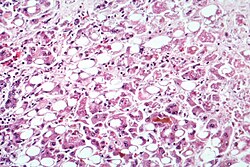

Alkohol i jetra

Bolest jetre uzrokovana alkoholom je najčešća bolest (ABJ). 90% alkohola se razgradi u jetri i to 0.1 promil na sat. Česti poremećaj je masna jetra, no to je reverzibilno. Ozbiljniji oblik ABJ-a je alkoholni hepatitis, karakteriziran stalnim upalnim promjenama i cirozom, koja je obilježena progresivnim ožiljkavanjem jetrenog tkiva. 10-35% alkoholičara razvije alkoholni hepatitis, a 10-20% dobije cirozu jetre. U SAD-u ciroza je na 7. mjestu uzroka smrti. Tijekom metabolizma alkohola u jetri nastaje i štetan produkt acetaldehid, a tu su i slobodni radikali, koji nastaju te tako oštećuju vitalne funkcije poput procesa stvaranja energije. Slobodni radikali mogu nastati kao obrambeni mehanizam uništavajući uzročnike infekcije, no opet može ih nastati previše tako da uništavaju zdrave stanice jetre. Alkohol također povećava prolaz štetnih bakterijskih spojeva poput endotoksina koji pak aktivira proizvodnju citokina. Citokin u jetri stvara simptome slične alkoholnom hepatitisu. Nastaje jedan začarani krug, što dovodi do upale, stanične smrti i ožiljkavanja jetre. Ožiljkavanje je "zaštitni znak" ciroze jetre. Proces kojim se razvija ciroza uključuje određene citokine i specijalizirane jetrene stanice (tj. zvjezdaste stanice). U zdravoj jetri te stanice služe kao skladište za vitamin A. Pod utjecajem citokina, zvjezdaste stanice rastu, gube rezerve vitamina A, i počinju stvarati ožiljkasto tkivo. Uz to, te stanice, uzrokuju stiskanje krvnih žila, smanjujući dovod kisika do jetrenih stanica.